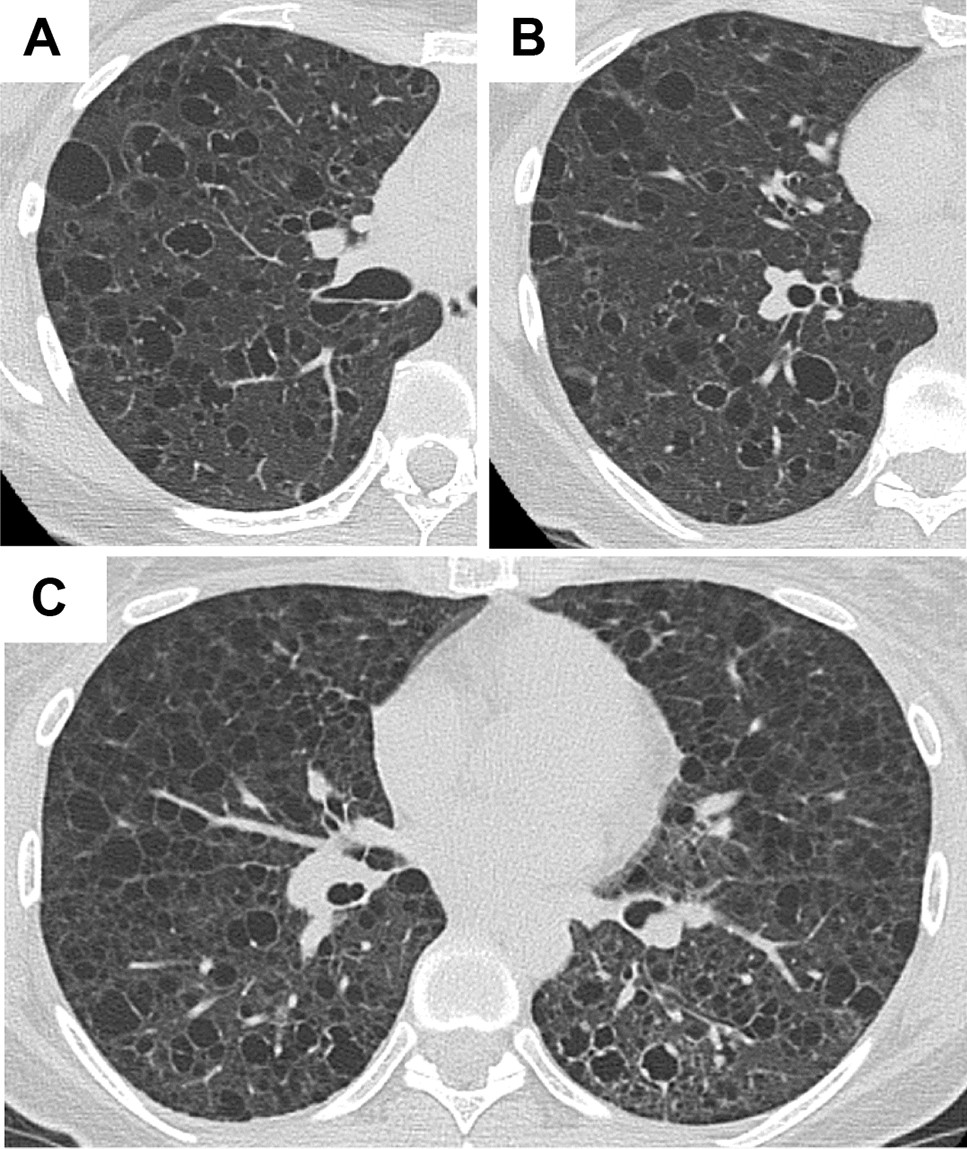

Figure 2

Representative HRCT images with common appearance and co-existence of cysts with irregularly thickened walls. (A,B) A 39-year-old female with S-LAM. She had a left pneumothorax and the diagnosis was made histopathologically. Some of the cysts had irregularly thickened walls showing a “dot-like appearance”. (C) A 39-year-old female with S-LAM. Lung parenchymal radiolucency around the cysts with irregularly thickened walls in the left lung decreased compared to the right lung, suggesting lymphatic congestion in the left lung. The diagnosis of LAM was made histopathologically.